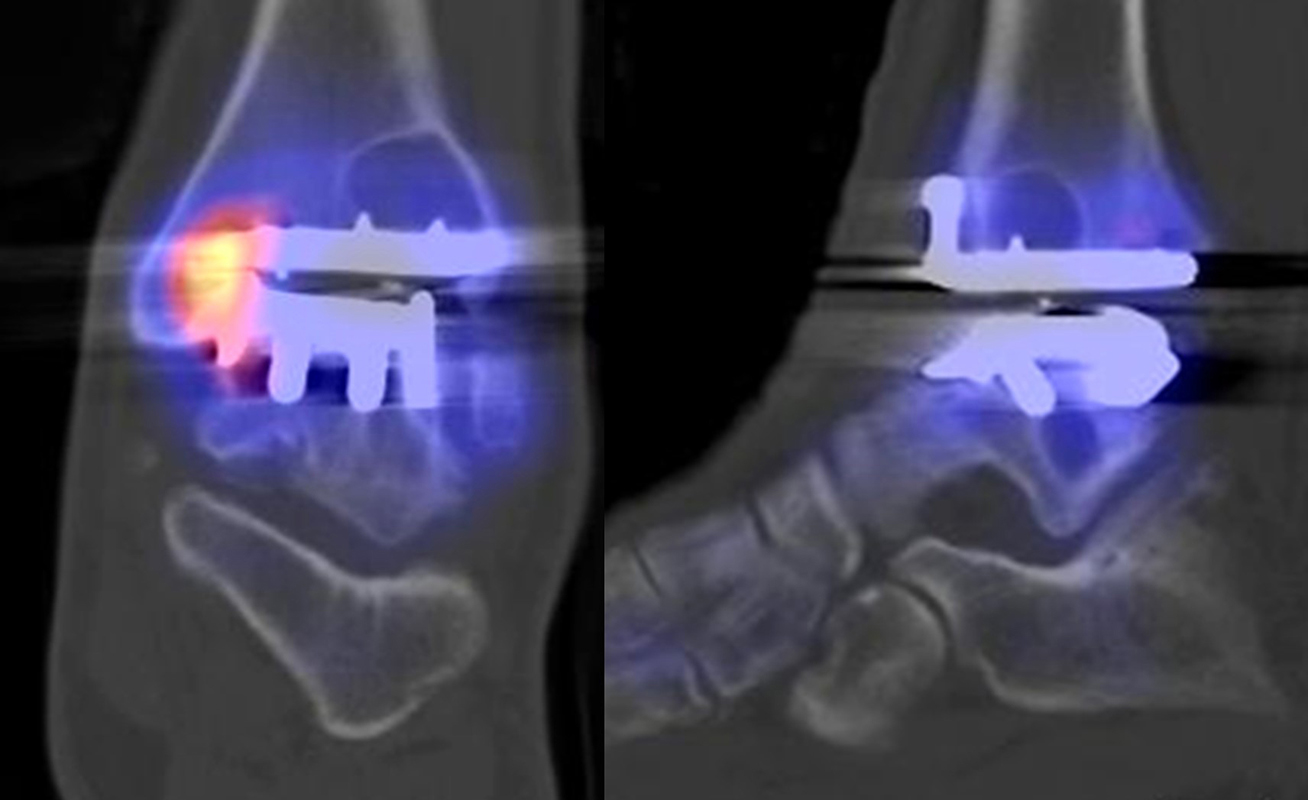

Beispiele für SPECT/CT-Untersuchungen nach OSG-TEP sind in den Abbildungen 6.1. bis 6.3. abgebildet.

Gurbani et al. evaluierten 37 Patienten mit schmerzhaften Sprunggelenkprothesen mit SPECT/CT und korrelierten die Ergebnisse mit klinischen und intraoperativen Befunden. Die SPECT/CT-Ergebnisse korrelierten zu 89,2 % (33/37 Pat.) mit der definitiven Diagnose. 28 Patienten wurden operativ revidiert und der Vergleich der SPECT/CT-Befunde mit den intraoperativen ergab eine Übereinstimmung von 92,9 % (26/28 Pat.). Die SPECT/CT identifizierte in den meisten Fällen aseptische Lockerungen (12/33 Pat.) und Impingement (11/33 Pat.). Seltenere Diagnosen waren Fehlstellungen (4/33 Pat.), Zystenbildungen (2/33 Pat.), subtalare Arthrosen (2/33 Pat.) und Infektionen (2/33 Pat.) 51.

Die Autoren beschreiben einen Fall, der neben einem Fokus am lateralen Malleolus auch eine starke flächige Anreicherung am talaren Prothesen-Knochen-Interface 17 Monate nach TEP-Implantation aufwies, so dass neben dem Verdacht auf ein laterales Impingement auch der Verdacht auf eine Lockerung der talaren Prothesenkomponente geäußert wurde. Intraoperativ bestätigte sich die Lockerung der talaren Prothesenkomponente nicht, sondern nur das laterale Impingement, welches mittels Debridement erfolgreich therapiert wurde 51. Da der Pat. bereits vor der TEP-Implantation eine Triple-Arthrodese erhalten hatte (welche im SPECT/CT unauffällig war), kann eine solche flächige Mehrspeicherung auch als weitgehend asymptomatische Stressreaktion gewertet werden.

Mertens et al. 52 berichten unter Anwendung eines standardisierten Auswerte-Schemas über eine Treffsicherheit von 96 % (Sensitivität 100 %, Spezifität 80 %) des SPECT/CT zur Diagnose der Ursachen für eine schmerzhafte Sprunggelenkprothese (n=24). Der SPECT/CT-Befund führte in 86 % zu einer spezifischen Therapie, welche in 83 % der Fälle zum Therapieerfolg führte.

Eine Analyse von Mason et al. 53 von 14 Patienten mit schmerzhaften Sprunggelenksprothesen, welche mittels SPECT/CT untersucht wurden, fanden in 13/14 Patienten ein SPECT/CT-Korrelat für die Beschwerden, wobei bei 12 Patienten der Fokus talar medial lokalisiert war. 8 Patienten wurden operativ revidiert und der Fokus entsprach einer verminderten bzw. fehlenden ossären Integration der talaren Prothesen-Komponente.